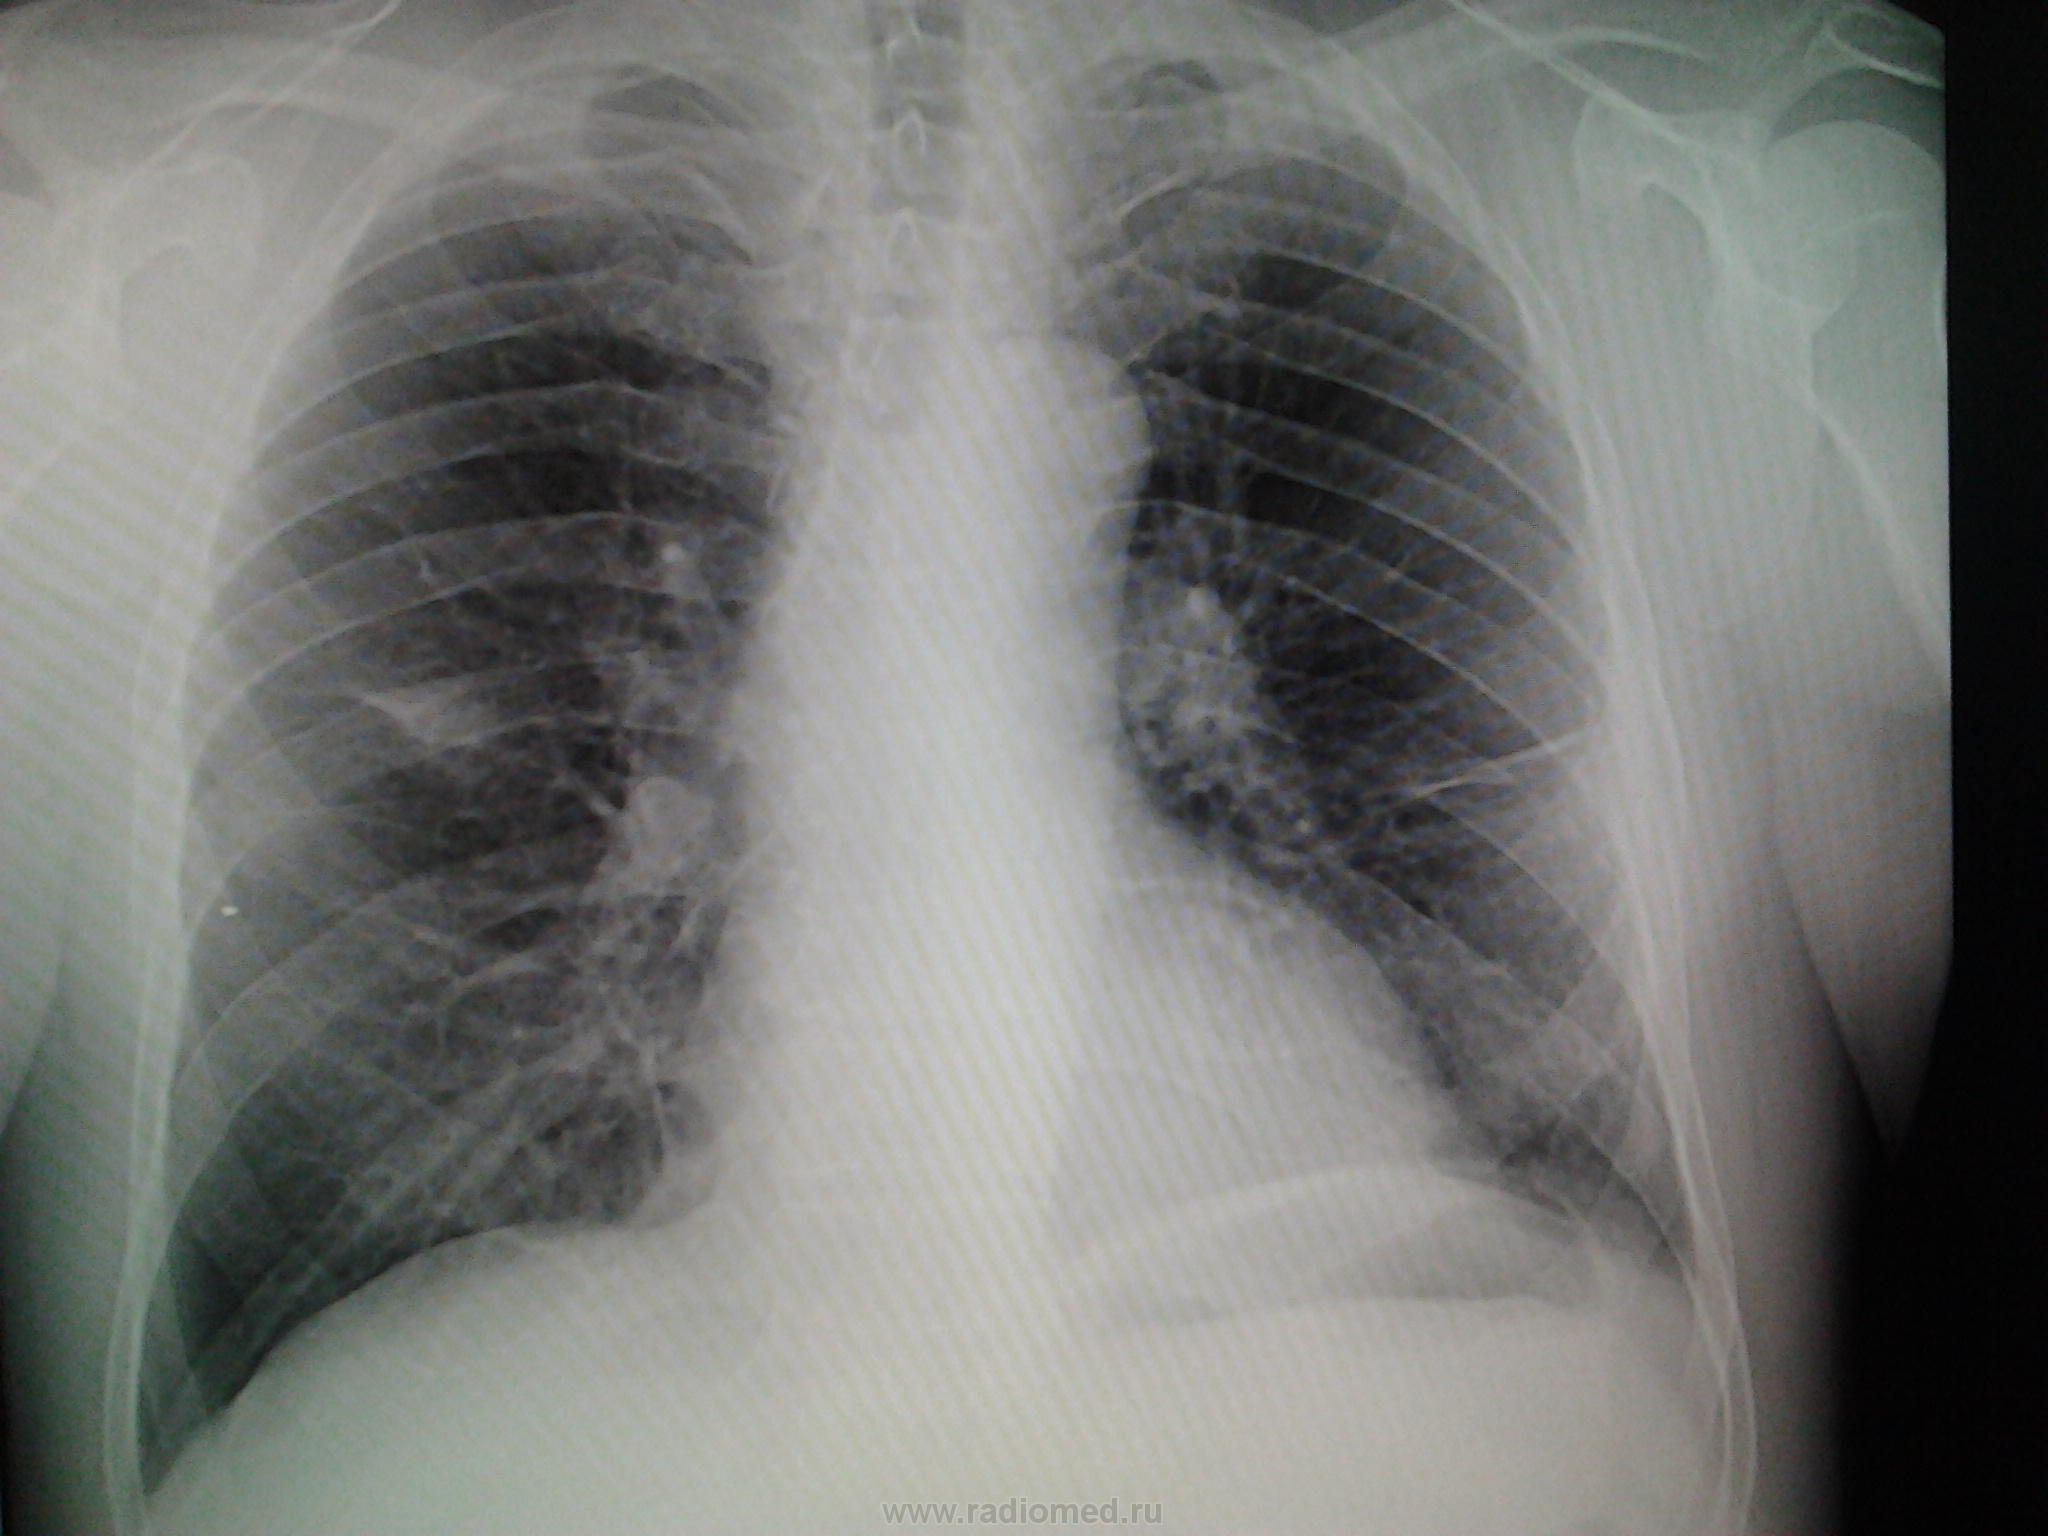

Мужчина 1956 г.р,проф.флг,жалоб со стороны легких не предъявляет,температура нормальная,посмотрела в амб.карте- последняя флг в 2008 году,там была норма,сейчас лечится у невролога по поводу межреберной невралгии.Можно ли расценить тень справа в тройке как фиброз?

Тут так сразу и не скажешь.Если свежего архива нет,надо наблюдать в динамике.Тень справа нехорошая,просится на томографию,желательно,компьютерную.Линейная тоже может внести некоторую ясность.

Крайне не красивый "фиброз". Рачком попахивает. Лучше сразу проконсультировать у онколога, а за одно уж и у фтизиатра.И контроль за ним обязателен.

Да уж,"фиброз" и впрямь какой-то подозрительный,отправлю на дообследование дядечку,тем более, кажется в тройке он

Да, в тройке.

Дообследуйте,не рискуйте.Тянуть опасно.

И здесь тоже, кажется, плохи дела, и опять в корне уже. А точно межреберная невралгия у него? И справа? Наводит на размышления. Поспрашивайте, если можно анамнез в ближайшие 3-5месяцев. Ничем не болел? Слева тоже изменения.